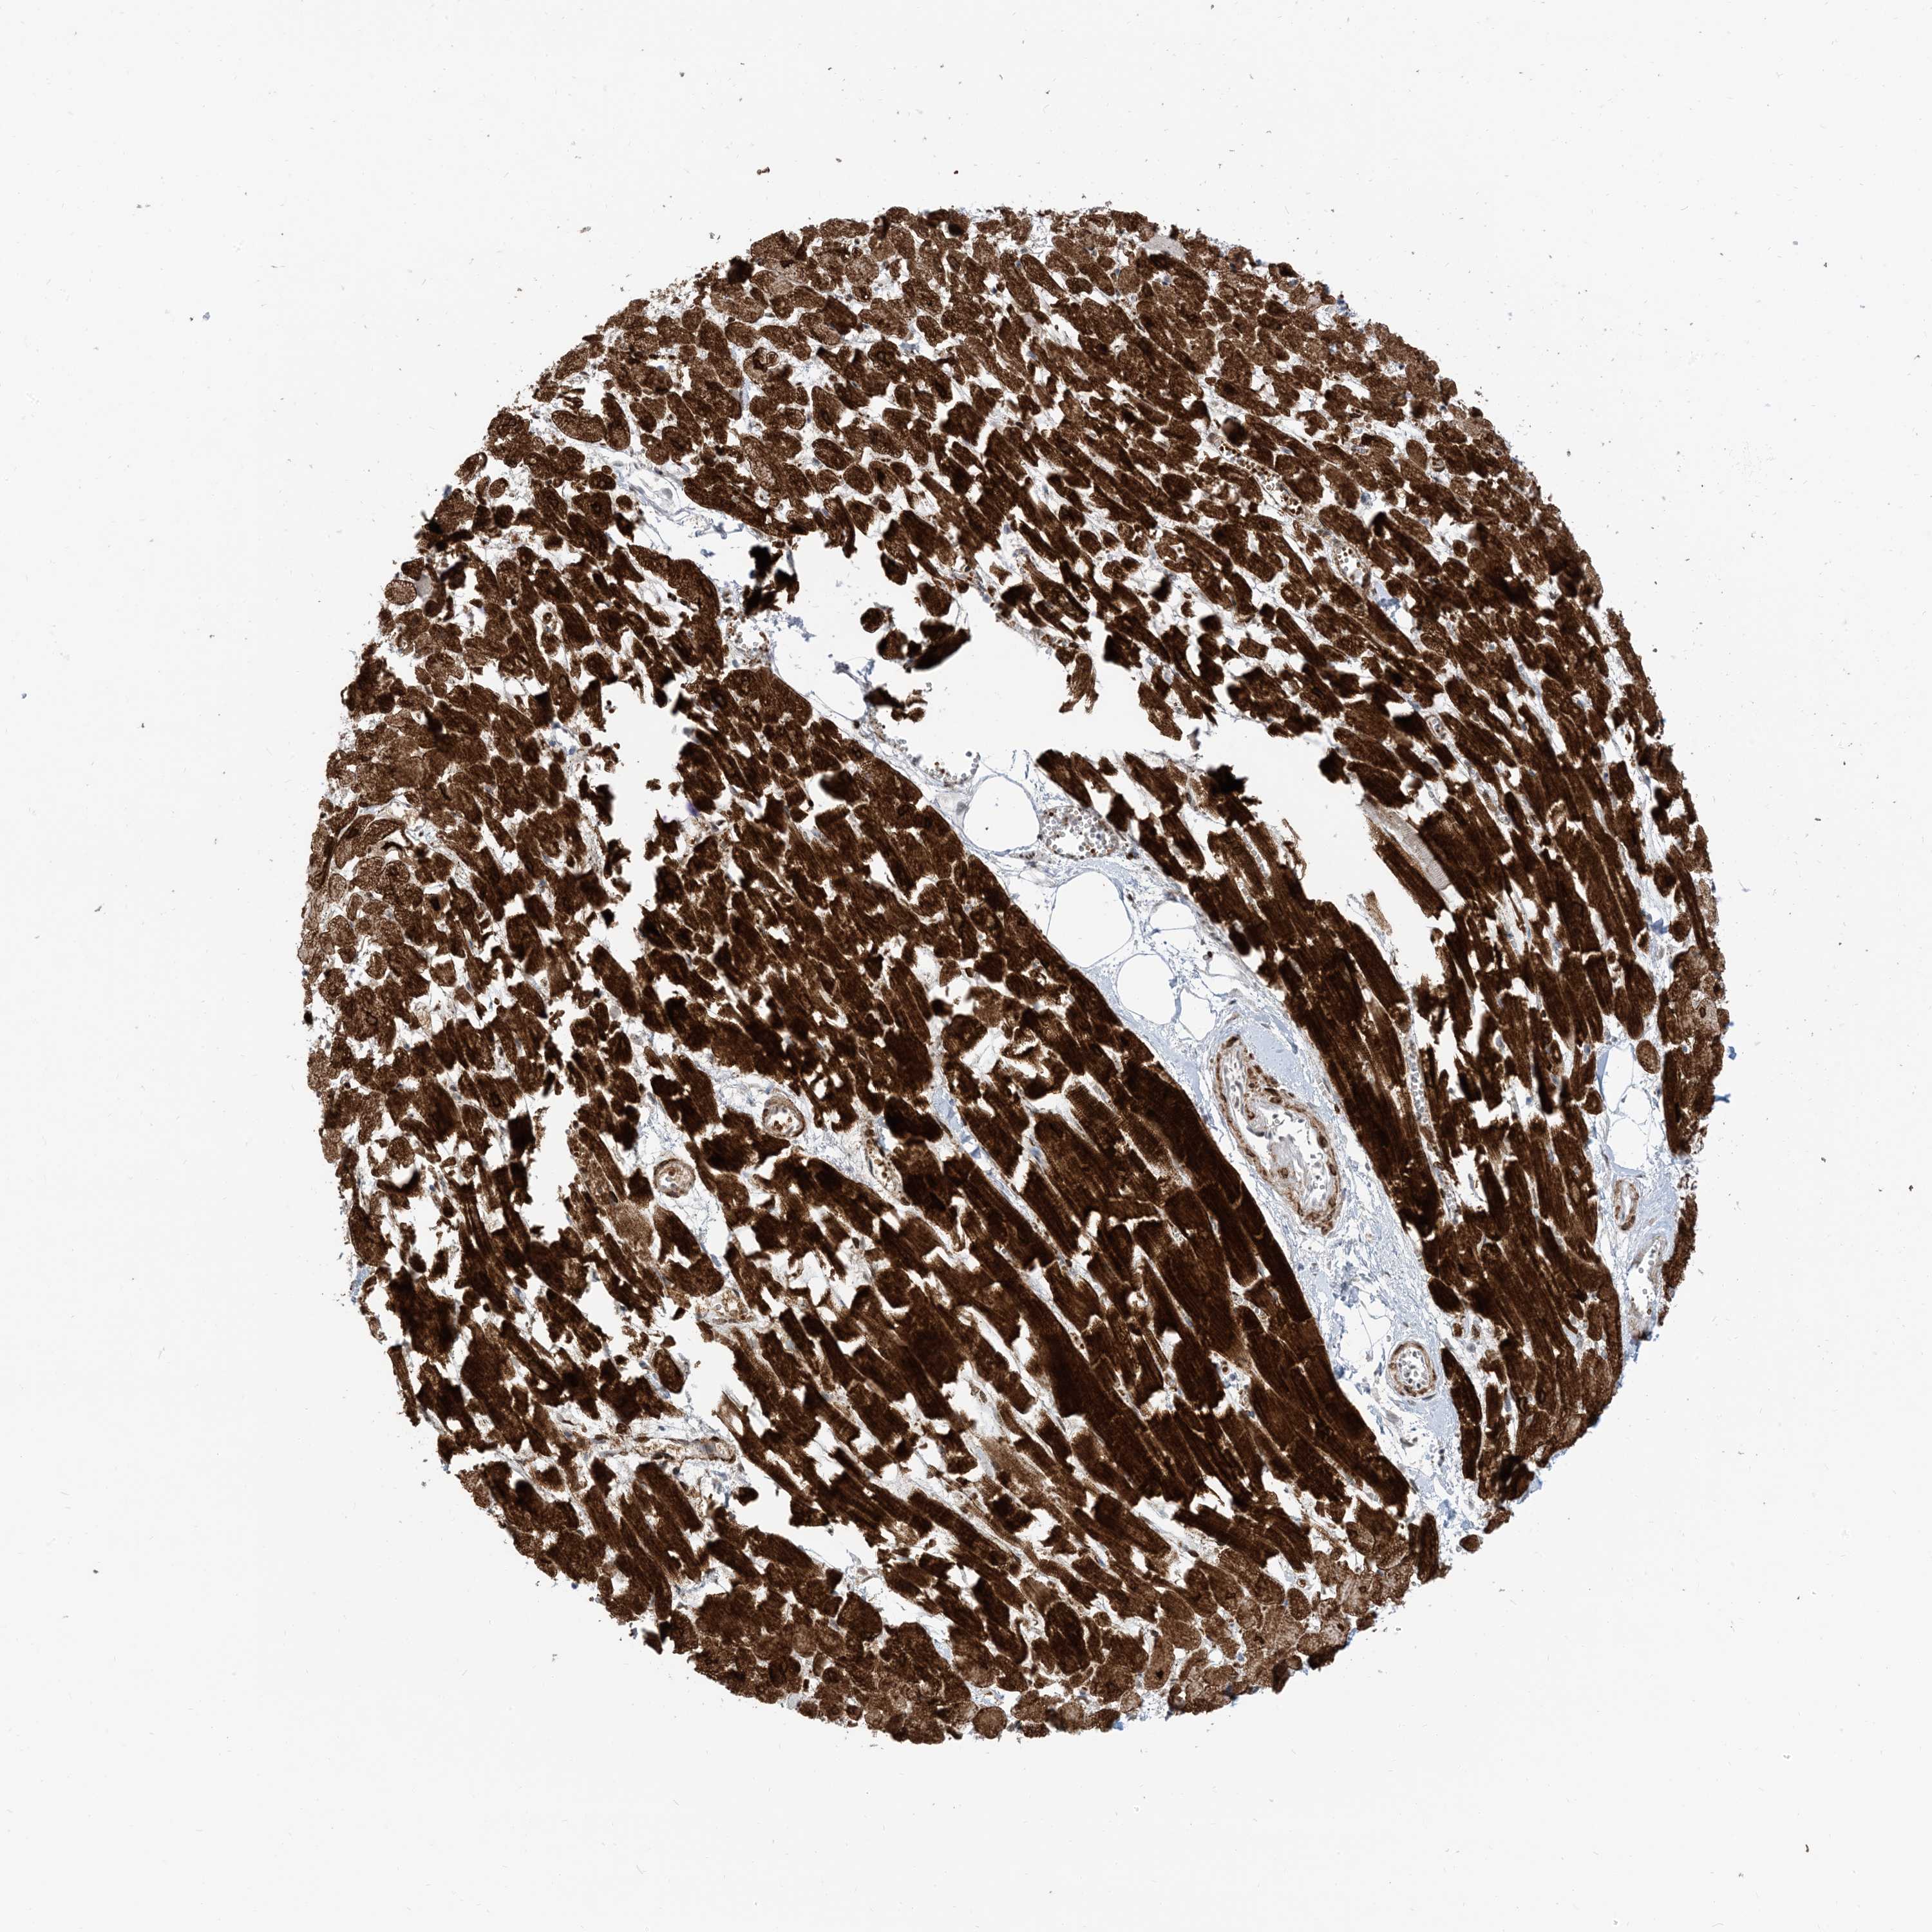

HEART MUSCLE - Antibody stainingi

Antibody staining in the annotated cell types in the current human tissue is reported as not detected, low, medium, or high, based on conventional immunohistochemistry profiling in selected tissues. This score is based on the combination of the staining intensity and fraction of stained cells.

Each image is clickable and will lead to virtual microscopy that enables deeper exploration of all samples and also displays staining intensity scores, fraction scores and subcellular localization as well as patient and tissue information for each sample.

Antibody HPA035491

Cardiomyocytes High